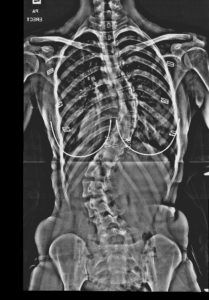

Scoliosis can be divided into primary and secondary, of which primary (unexplained cause) accounts for 80%. Recent studies have found that primary scoliosis is mostly genetic inheritance, and a few are environmental factors. Most patients do not experience any pain, and only a few severe patients have difficulty in breathing because their lungs are squeezed by the curved spine. Usually, postural assessment and Adam's test can be used to check whether there is scoliosis, and X-ray can determine its severity. The spine will curve to the left or right, accompanied by rotation and tilting front and back with "3D" abnormalities, which are prone to continue to deteriorate during adolescence (bone growth period), so it is common in adolescents who are 10 years old to fully-grown adolescent.

- Severe: Patients with an angle greater than 50 degrees and have not yet completed their growth development (there is a greater chance that they will continue to deteriorate), surgery is needed to avoid the scoliosis of the spine from squeezing the organs and causing life to be in danger.